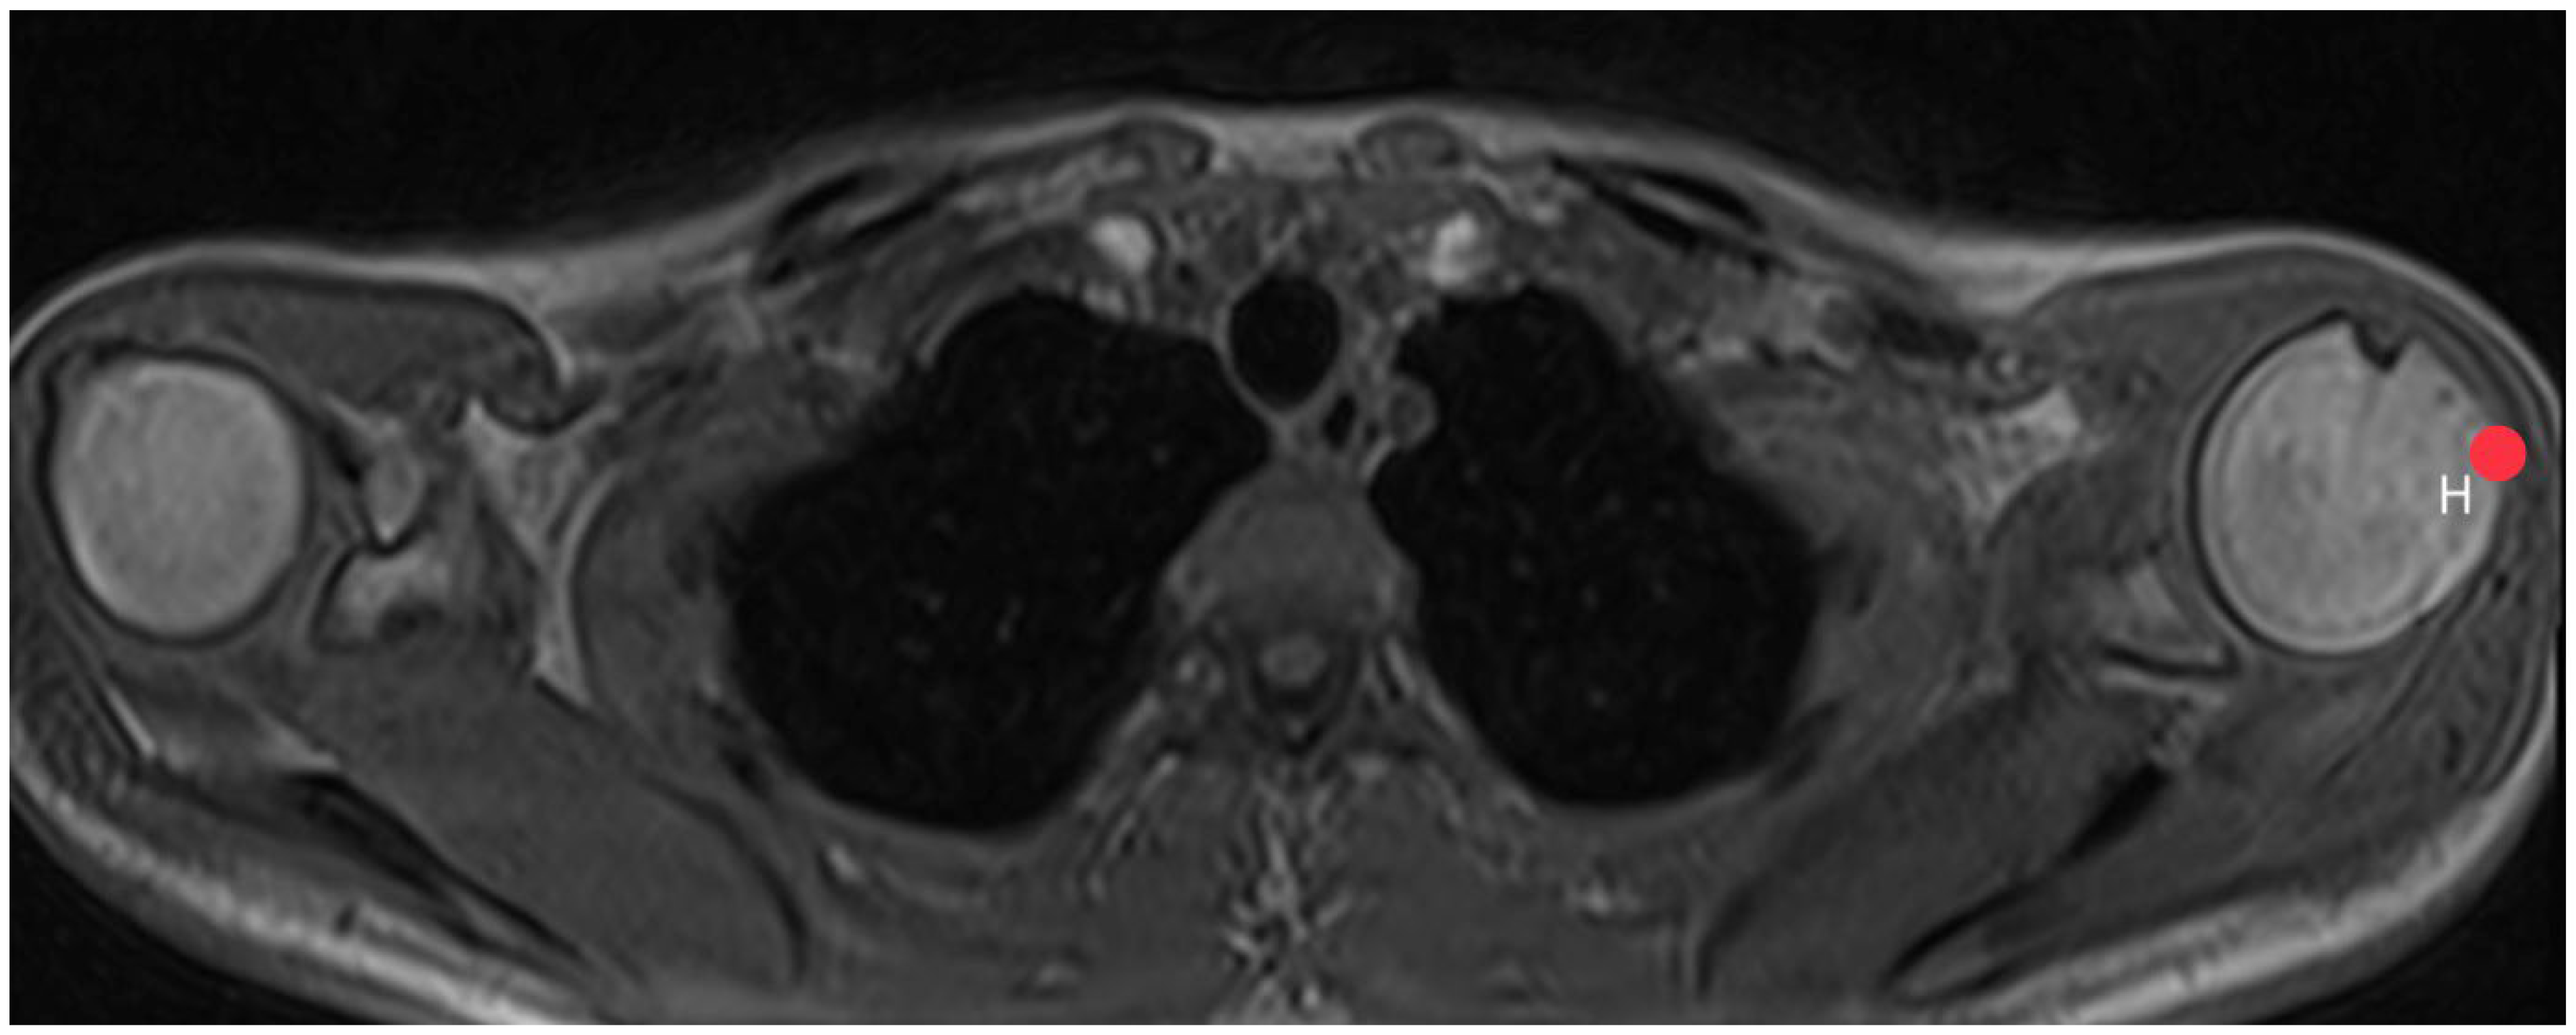

2.3. Acromion Index (Figure 1)